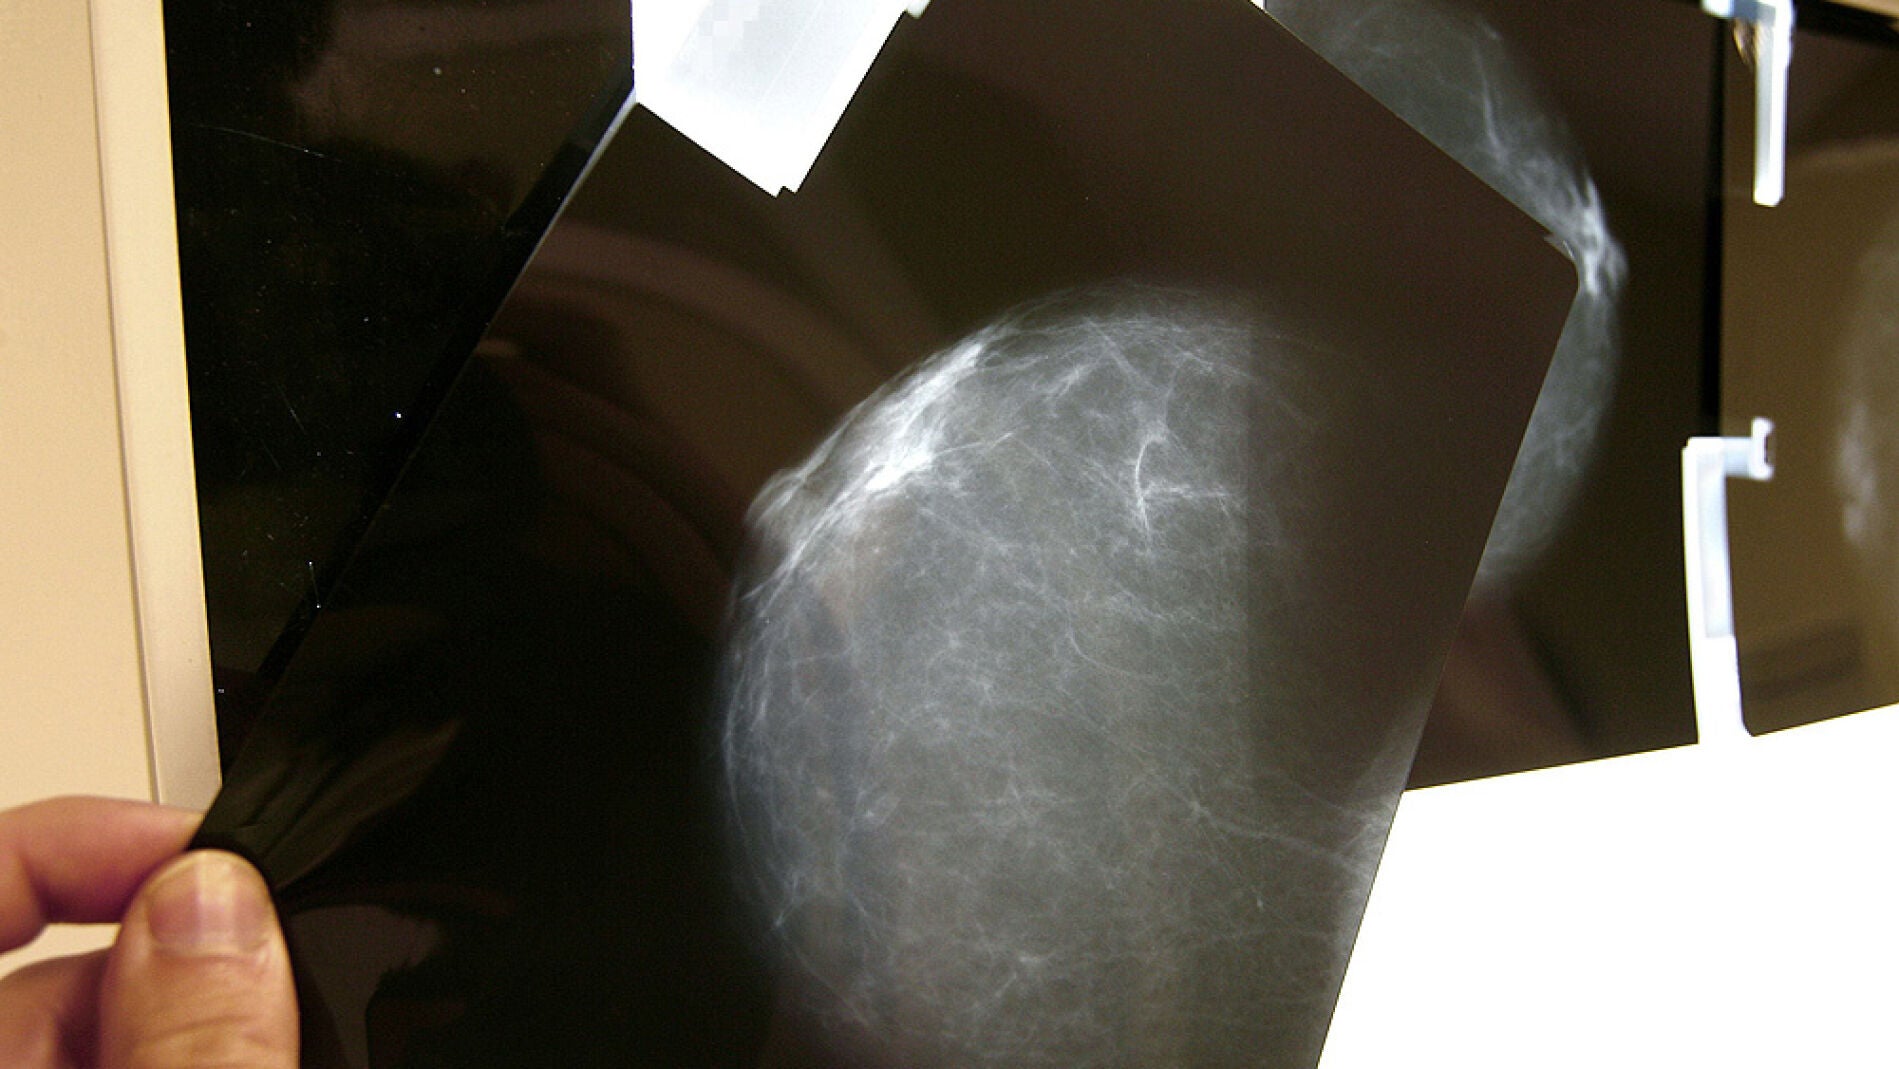

Comienza en Pamplona un ensayo de vacunas para evitar las recaídas del cáncer de mama

La Clínica Universidad de Navarra ha anunciado el inicio de un ensayo clínico para comprobar la eficacia de la aplicación de vacunas personalizadas para reducir las recaídas en cáncer de mama. Las vacunas están elaboradas con células dendríticas del sistema inmune de la paciente y estimuladas con su propio tumor para reducir la progresión del cáncer de mama en un subgrupo determinado de esta enfermedad, aquel en el que las células tumorales no expresan la proteína HER2.